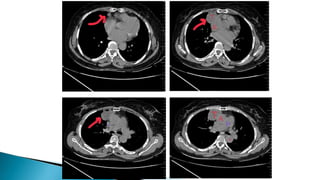

• Chest CECT scan is the imaging procedure of

choice in patients with MG.

– Thymic enlargement should be determined because

most enlarged thymus glands on CT scan represent

a thymoma.

– CT scan with intravenous contrast dye is preferred

– to show the relationship between the thymoma and

surrounding vascular structures,

– to define the degree of its vascularity, and

– to guide the surgeon in removal of a large tumor,

possibly involving other mediastinal structures

• Chest CECTscan is the imaging procedure of choice in patients with MG. – Thymic enlargement should be determined because most enlarged thymus glands on CT scan represent a thymoma. – CT scan with intravenous contrast dye is preferred – to show the relationship between the thymoma and surrounding vascular structures, – to define the degree of its vascularity, and – to guide the surgeon in removal of a large tumor, possibly involving other mediastinal structures